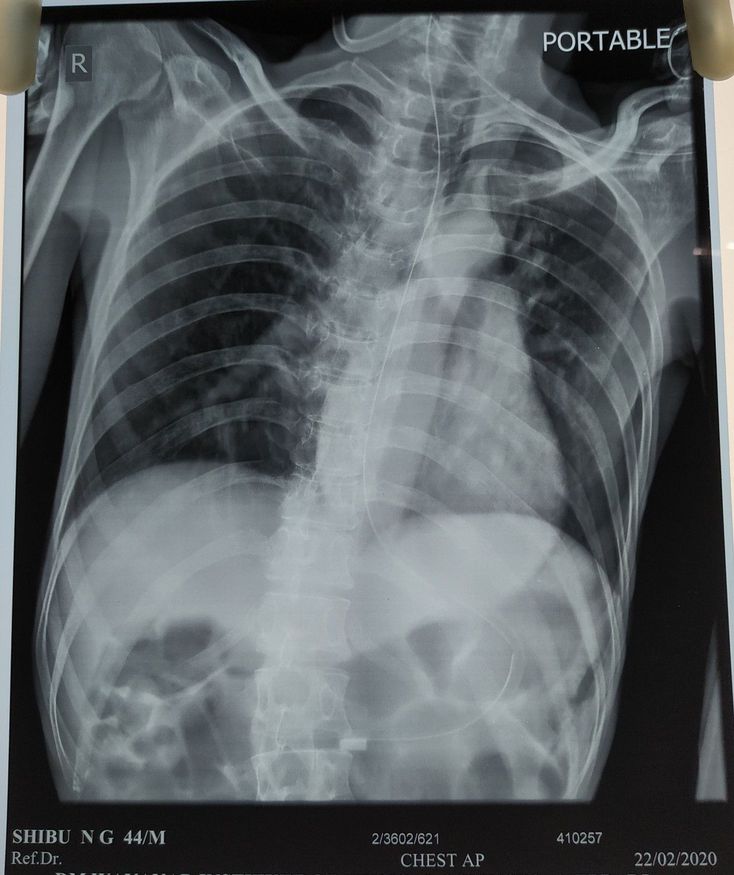

A 45 yr old male or , who is a k/c of ALS with Bulbar dysfunction since 5 years, now presented with breathing difficulty since one day . Pt also c/o fever , intermittent type since one day . Past history of stopping of taking medication since last 1 year . No h/o DM, HTN, Seizure , Thyroid dysfunction .

I think some patchy infiltration.maybe a kind of TB. Aortic knob its a little big i think

Yeah, The pt was diagnosed with Aspiration pneumonia and currently under treatment . Thanks for pointing your findings doctor.